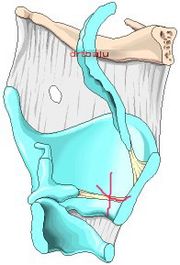

| 12:14, 22 October 2018 | Fract larynx.jpg (file) |  |

60 KB | Drtbalu | |